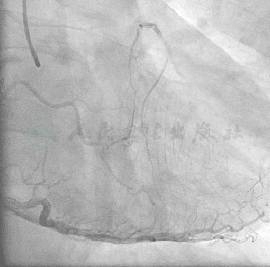

冠状动脉造影结果

经右侧桡动脉径路,6F血管鞘,造影结果发现:LM正常(图1);LAD在S1发出处完全闭塞,看不到断端(图2);LCX正常,向LAD形成侧支循环1级,心外膜途径,极度迂曲,直径较大(图3)。RCA正常,向LAD形成侧支循环1级,间隔支途径,迂曲较少,直径偏小(图4)。

图1 LM正常